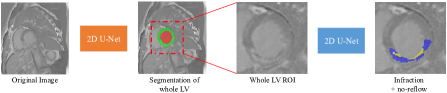

This paper focuses on both healthy and pathology pathologic myocardium segmentation from the delayed-enhancement cardiac MRI. One of the main challenges is how to exploit rich and reliable information regarding the pathological as well as morphological information of the myocardium. To this end, we design a cascaded framework that comprises two 2D U-Net to segment the left ventricle and myocardium, and the pathology regions, respectively. Figure 2 presents the whole pipeline of the proposed method. Specifically, the proposed method contains three steps111In step 1 and step 3, the networks are trained end-to-end, while the whole framework is not end-to-end.:

• Step 1 (whole LV segmentation). Train a 2D U-Net [10] on the original CMR images to segment the whole LV (including left ventricular blood pool and myocardium);

• Step 2 (creating ROI). Crop LV region of interest (ROI) from the original CMR images based on the segmentation results in step 1. In this way, the unrelated background can be excluded;

• Step 3 (infraction and no-reflow segmentation). Train a new 2D U-Net to segment the infraction and no-reflow from the ROI images.

Refer to caption

Figure 2: Pipeline of the proposed method. we first use a 2D U-Net to segment the whole LV (left ventricle), including LV blood pool and myocardium. Then, we crop the LV region of interest (ROI). Finally, a new 2D U-Net is used to segment the infraction and no-reflow areas.